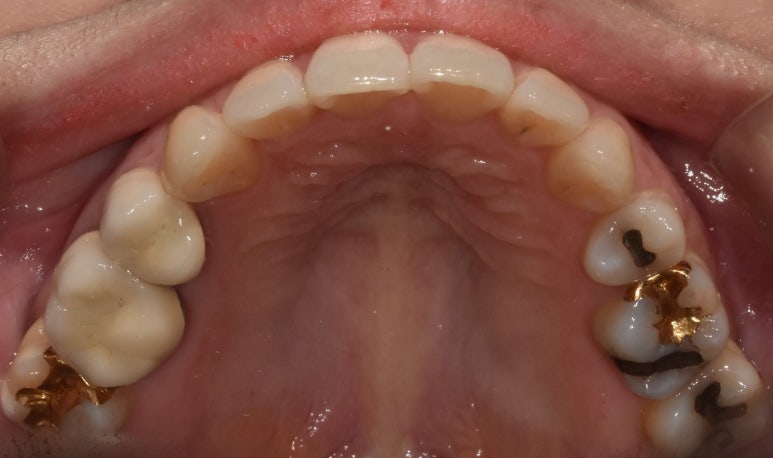

골드 인레이 예시 (오른쪽)

골드인레이 예시

가장 큰 단점은 누런 색상으로 인해 보기에 좋지 않다는 점과, 치아의 크랙(균열) 발생 가능성이 크다는 점을 꼽을 수 있습니다.

어금니에 골드인레이를 하게 되면 금속의 누런 색상이 눈에 잘 띄기 때문에 보기에 좋지 않다는 점,